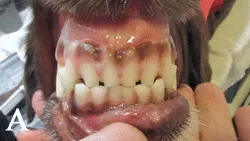

(A) Frontal view of lower incisors showing generalized severe dental wear. Arrows show all teeth with pulp exposure, which indicate that treatment in needed. Extractions were recommended, although root canal therapy could be considered if roots are not resorbing.